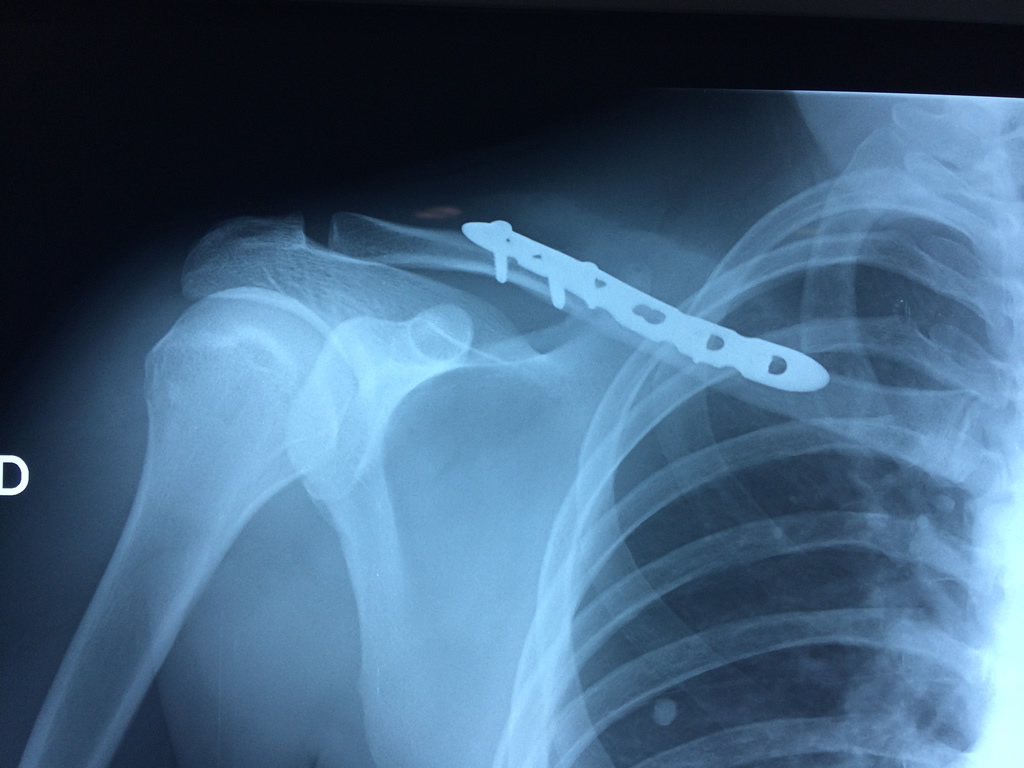

Cirugías de Codos - Clavícula

La clavícula es un hueso largo, con forma de "S" itálica, situado en la parte anterosuperior del tórax. Junto con la escápula forman la cintura escapular. Se puede palpar por toda su longitud y se extiende del esternón al acromion de la escápula, siguiendo una dirección oblicua lateral y posterior.